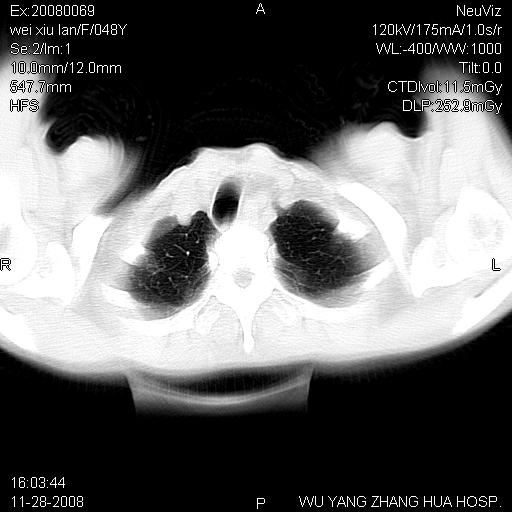

标题: CT16847:女,48岁,咳嗽,发热两日,平常偶有上腹部不适。 [打印本页]

标题: CT16847:女,48岁,咳嗽,发热两日,平常偶有上腹部不适。

能否考虑食管裂孔疝?请老师们多多指教。

支持左侧膈疝,心脏受压右移.

胃、脾脏及部分肠管明显升高,并压迫心脏移位,

首先考虑:左侧膈疝。

左侧胸腔内见胃肠及脾脏影

支持膈疝